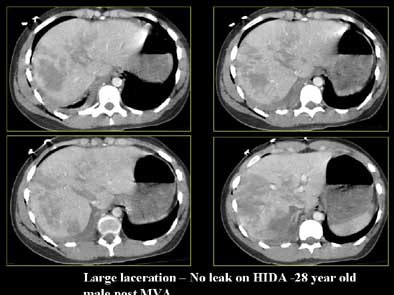

Twelve patients had lacerations that extended to both the medial and lateral surfaces (mean size 5.8 cm). Five of these patients had an active bile leak (mean size 6.8 cm). Only one patient with a bile leak had an extension to the lateral surface of the liver only.

Eighteen patients had lacerations of the central and peripheral portions of the liver (mean size 6.8 cm), of which 4/18 had an active bile leak (mean size 7.3 cm).